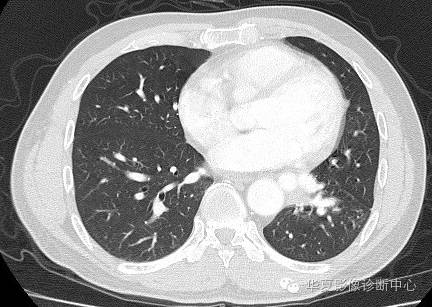

| 病史资料: | 男.51岁。无症状,体检就诊。 |

| 影像表现及分析: | 影像表现:定位左下叶;左下叶体积缩小,整体密度增高,支气管分布正常,其内见血管增多,但是走形正常,未见杂乱、迂曲的血管影;血管连向肺门下方软组织密度结节灶,结节与主动脉分界不清,增强后,见降主动脉发出异常粗大血管供血整个左下叶,左下肺动脉细小。 |

| 确诊依据: | CTA明确左下叶供血动脉为降主动脉发出 |

异常体动脉供应正常下肺基底段完整含义为起源于降主动脉的异常动脉供应下肺基底段,而基底段支气管树和肺实质正常,同时基底段肺动脉缺如或狭窄【大部分缺如(完全型),部分狭窄(不完全型)】;95%以上累及左下肺,因此也称为异常体动脉供应正常左下肺基底段。 病因尚未明确,可能是胚胎发育时期供应肺芽的背主动脉原始小分支退化不全,与肺实质形成异常连接,并影响肺动脉与肺血管床连接而导致此部位肺动脉发育不良,而支气管、肺组织的发育未受影响。本病的病理生理基础为左向左的分流,体动脉供应的肺组织充血,体循环的高压可增加肺血管床的压力和左心负荷,同时也增加肺循环量和压力而增加右心负荷,导致各种临床症群。本病可无临床症状,部分患者可有咯血、呼吸道感染、呼吸困难、充血性心力衰竭。 影像表现:左肺下叶体积缩小,整体密度稍增高,支气管树走形、分布正常,血管增多、稍增粗;增强后显示左下肺动脉幼小,甚至不发育;下叶由主动脉发出的粗大血管供血。 |